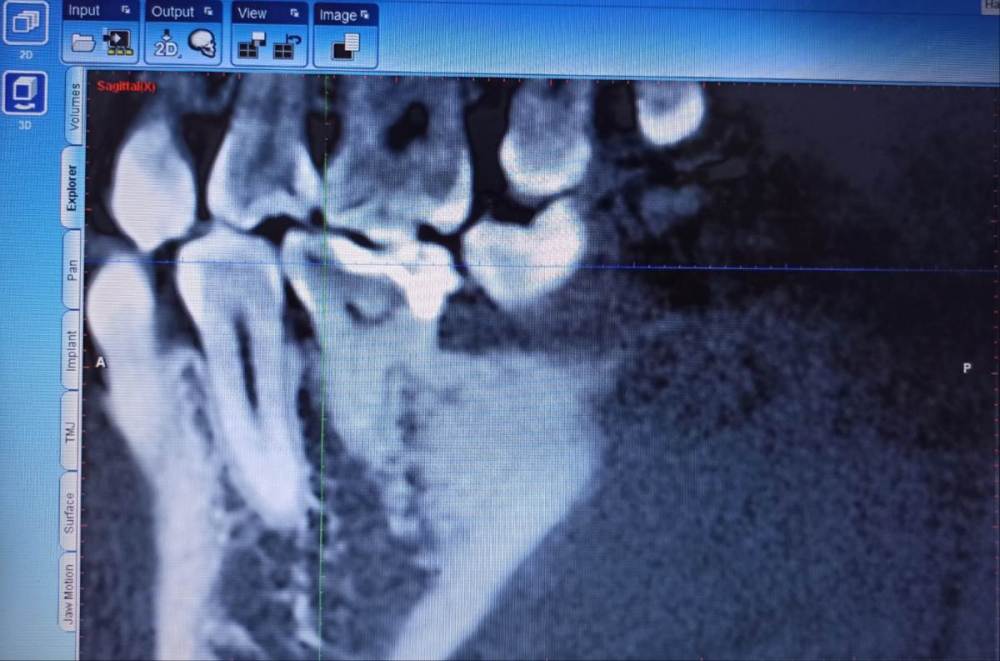

Привет, вопрос к уважаемым специалистам - Дилемма, можно ли спасти-вылечить пломбой или только коронку ставить,т.е. =умерщвлять?

Зуб нижней челюсти справа.

Снимки из КТ 2019-го года, и рентген лета 2022г.

Пломба ~2015-го.

@IvanK такие истины понятны, но вот напрягает, что уже на КТ старом вижу,что как будто пломба прямо на пульпе ...и тогда то ли я вижу совсем не то,то ли действительно так - и значит что снимая эту пломбу, точно же придется "умерщвлять"?

То есть кроме того снаружи видно что пломба большая и кариес под нее "подлез", увидел эту непонятную темноту, как будто пульпу, переходящую в пломбу и напрягся так сказать